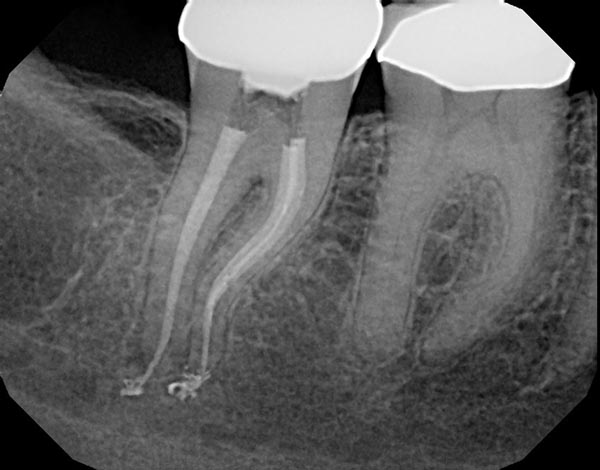

Fig. 4a: Preoperative image of tooth #31 with an irreversible pulpitis. The mesial roots have a subtle “S”-shaped curve and the preoperative working length was estimated to be 23mm. It was also assumed preoperatively that the MB and ML canals would be in close approximation or connected in the apical half of the root. This anatomy requires a flexible and efficient instrument with a good degree of torque strength. Fig 4b: Instrumentation was completed with Vortex Blue from Dentsply Sirona, a 500rpm, constant tapered file with excellent cutting efficiency. The postoperative image shows the files were able to follow the natural curves of the canal in multiple planes as the MB and ML canals joined in the apical half of the root.

Fig. 4a

Fig. 4b